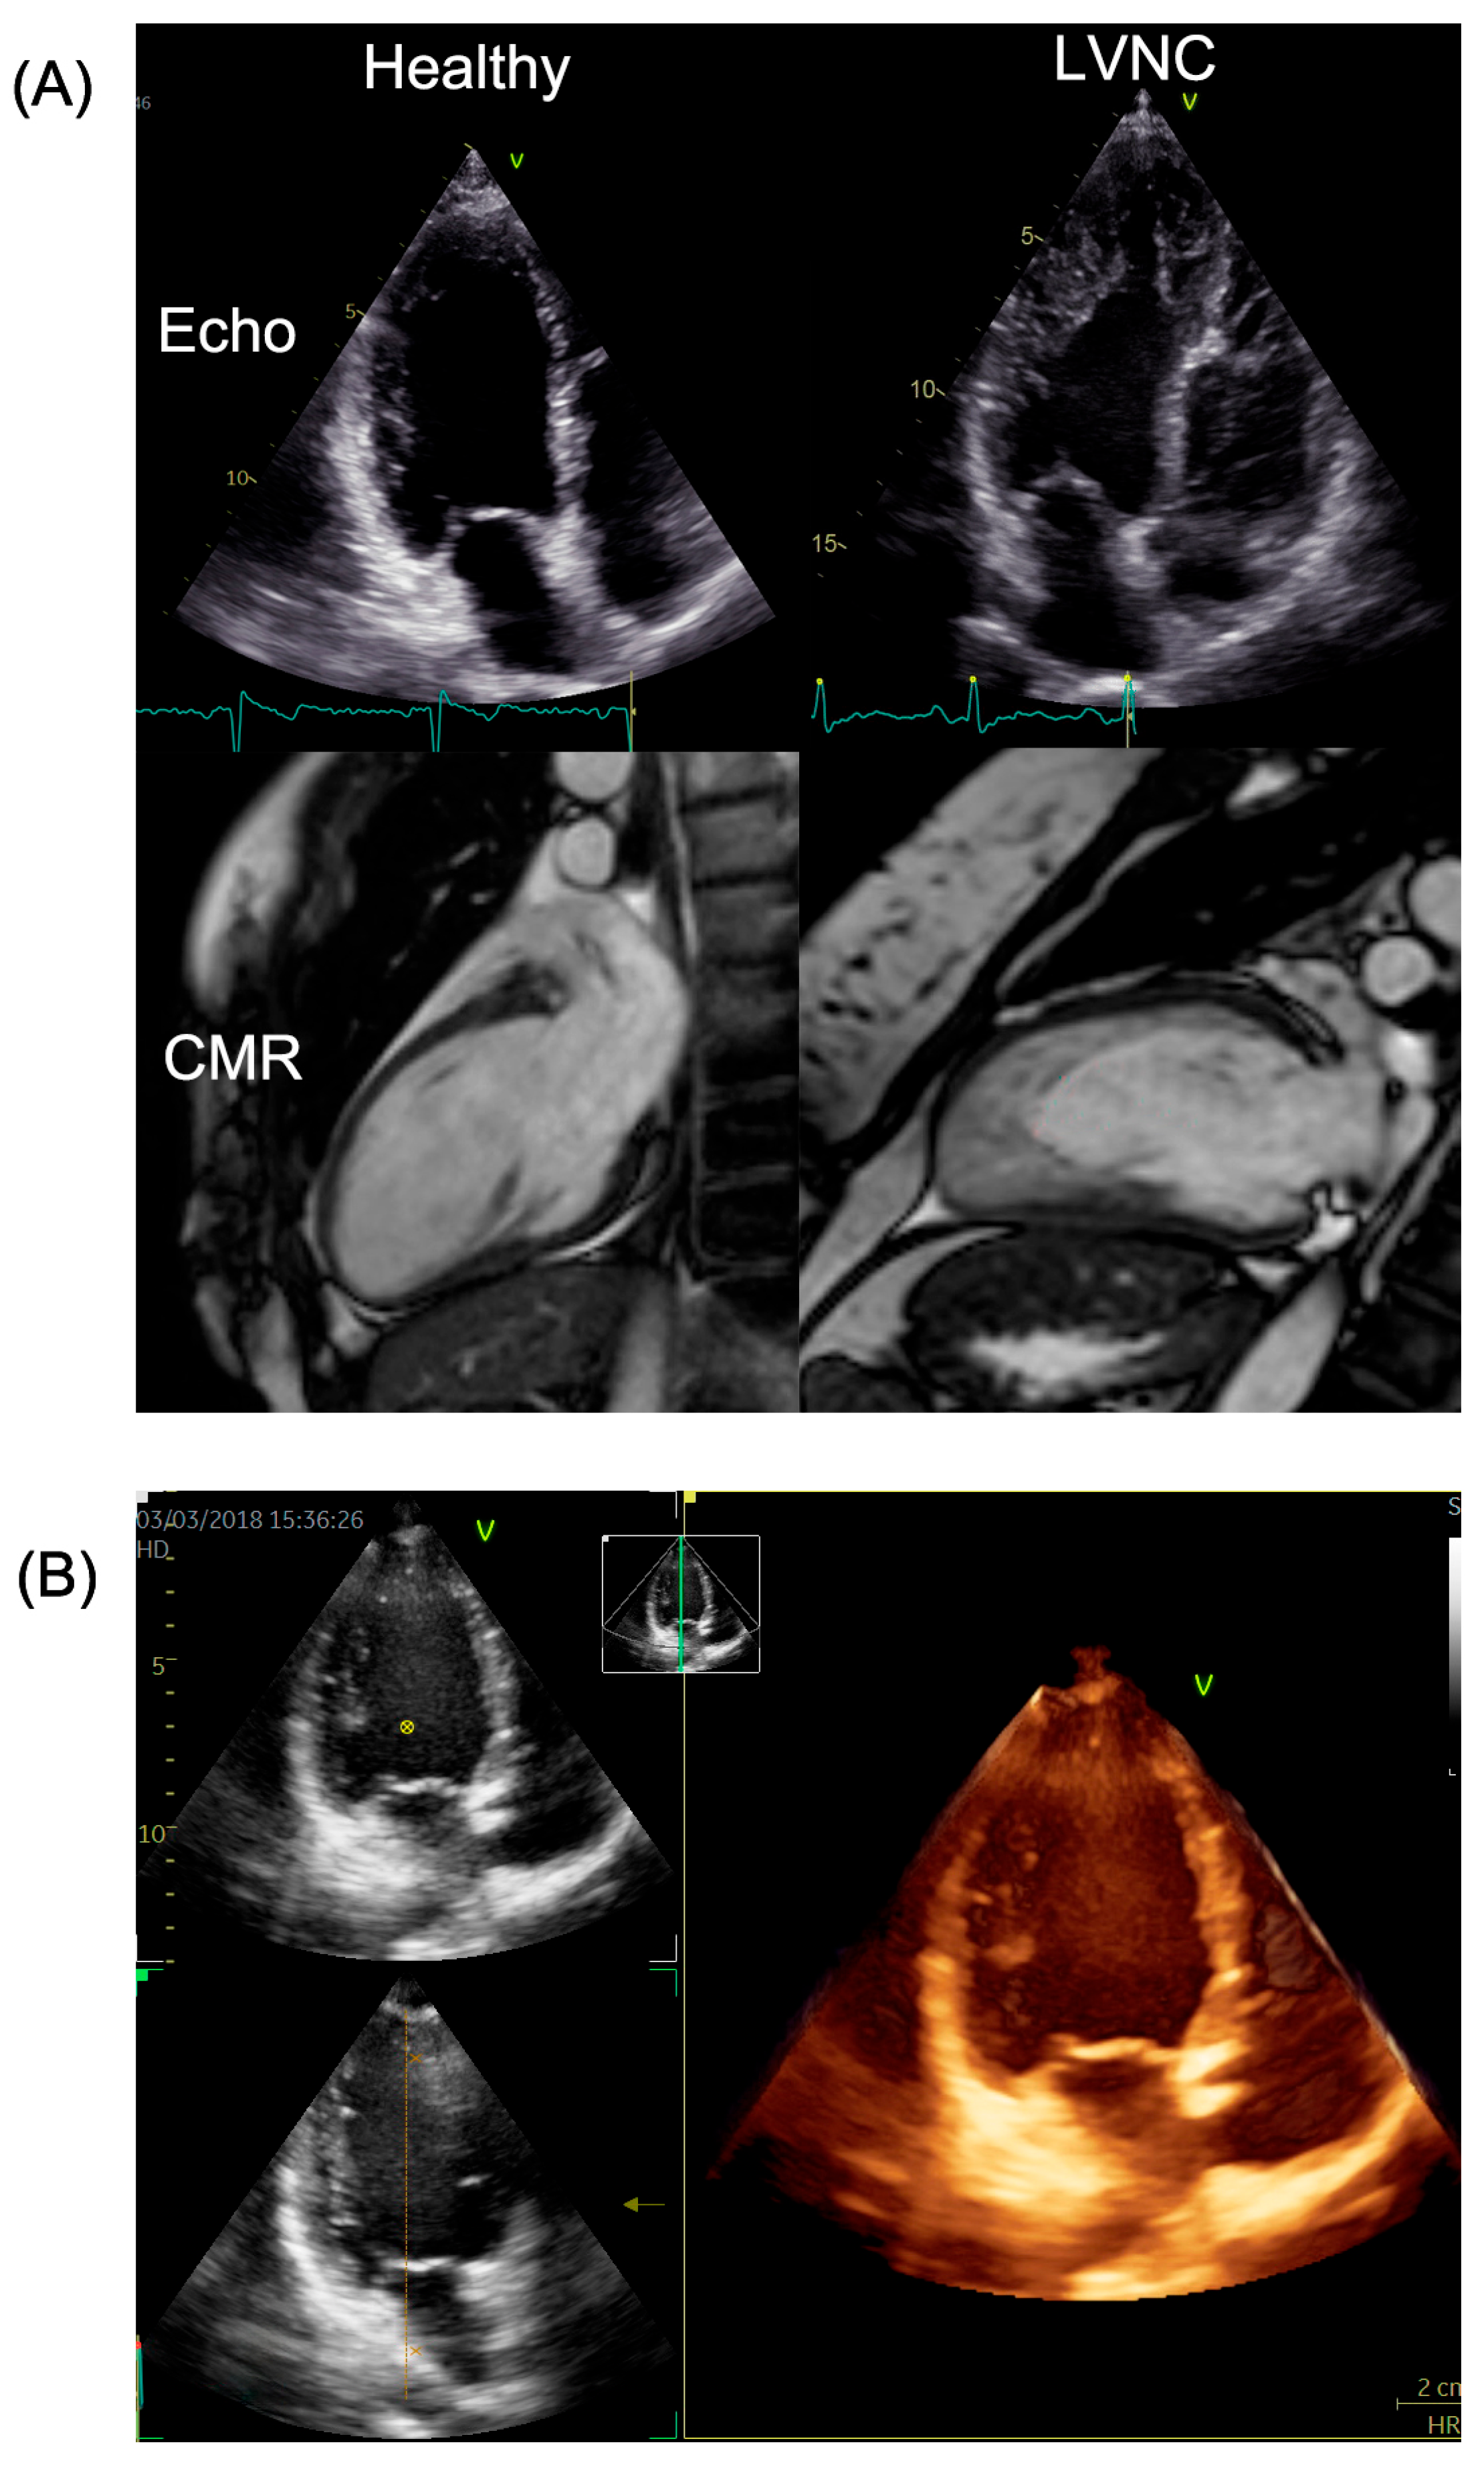

Excessive left ventricular trabeculation can be examined with multiple imaging modalities, of which cardiac magnetic resonance (CMR) is considered the gold standard for evaluating the huge amount of apical trabecular meshwork and establishing the diagnosis [1]. In certain cases, left ventricular noncompaction morphology (LVNC) develops to heart failure, emphasizing the significance of risk stratification and monitoring patients when deemed necessary. The deterioration of LVNC can be indicated by an increase in LV volumetric parameters and a decrease in LV functional parameters; however, the optimal modality for follow-up of this population remains unclear. Although CMR is known to be superior to echocardiography in measuring function and volume [2], the more readily available two-dimensional transthoracic echocardiography (2D_TTE) has a longer history in deformation analysis, which yields detailed information about subclinical functional changes of the LV. The optimal follow-up method should have a good cost–benefit ratio and be easily accessible and patient-friendly, such as modern three-dimensional transthoracic echocardiography (3D_TTE). This method has several advantages over two-dimensional LV strain measurements, as 3D strain values are derived from the entire LV myocardium, yielding more accurate estimates of global and regional LV function from a single beat image; thus, it is an easy-to-use option [3]. CMR and echo images of healthy and LVNC subjects are shown in Figure 1.

Figure 1.

(A) 2D echo and CMR images of a healthy and an LVNC patient. (B) 3D echo image of a LVNC patient. LVNC: left ventricular non-compaction; CMR: cardiac magnetic resonance imaging. The orange line in figure (B) marks the 90° axis in the 3D echo image.